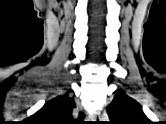

问题 女,47岁,下颈部触及一包块约5年余,CT如图所示,最可能诊断为()

选项 A.滑膜肉瘤 B.血管瘤 C.神经鞘瘤 D.副神经节瘤 E.巨淋巴结增生症

答案 C